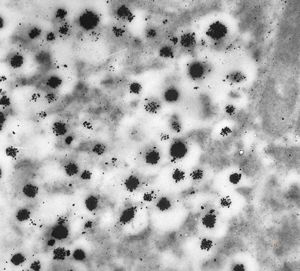

F,68y. | APUD carcinoma (Bodian siver impregnation)